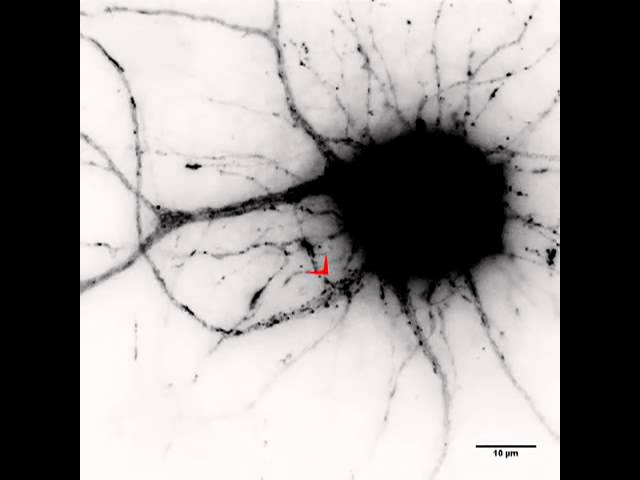

Везикулы представляют собой небольшие пузырьки, слегка приподнятые над поверхностью кожи. Их диаметр равен 1-5 миллиметров.

В самом начале своего развития везикулы на коже, фото которых можно увидеть ниже, покрыты пленкой эпидермиса. Кожа вокруг пузырьков воспалена и гиперемирована. После вскрытия на коже образуются мокнущие эрозии красноватого цвета.

Расслоение эпидермиса происходит из-за разрыва связей между клетками, который происходит под действием скопившейся жидкости.

Внешне такое проявление, как везикулы, представляют собой относительно небольшие новообразования, которые выступают над поверхностью кожи. Внутри них находится жидкое содержимое, которое может быть прозрачным либо слегка мутным. Образующиеся в виде круглых новообразований, везикулы имеют форму и размеры булавочной головки либо горошины.